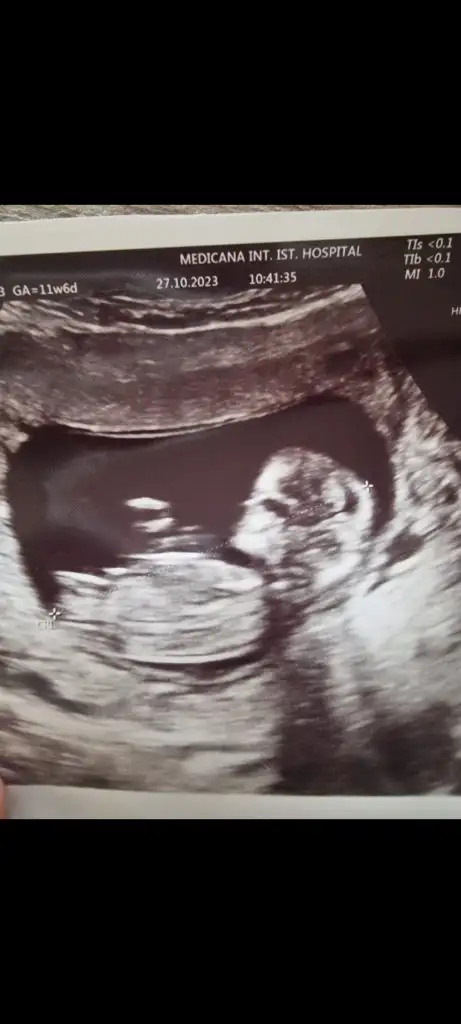

Bunlarada bakar mısınız lütfenErkek canım

Bunlarada bakar mısınız lütfenEvet erkek bu bebiş

Bunlarada bakar mısınız lütfenNub teorisi benim 2 oğlumda doğru çıktı. Bu bebiş kıza benziyor

Nub teorisi benim 2 oğlumda doğru çıktı. Bu bebiş kıza benziyor